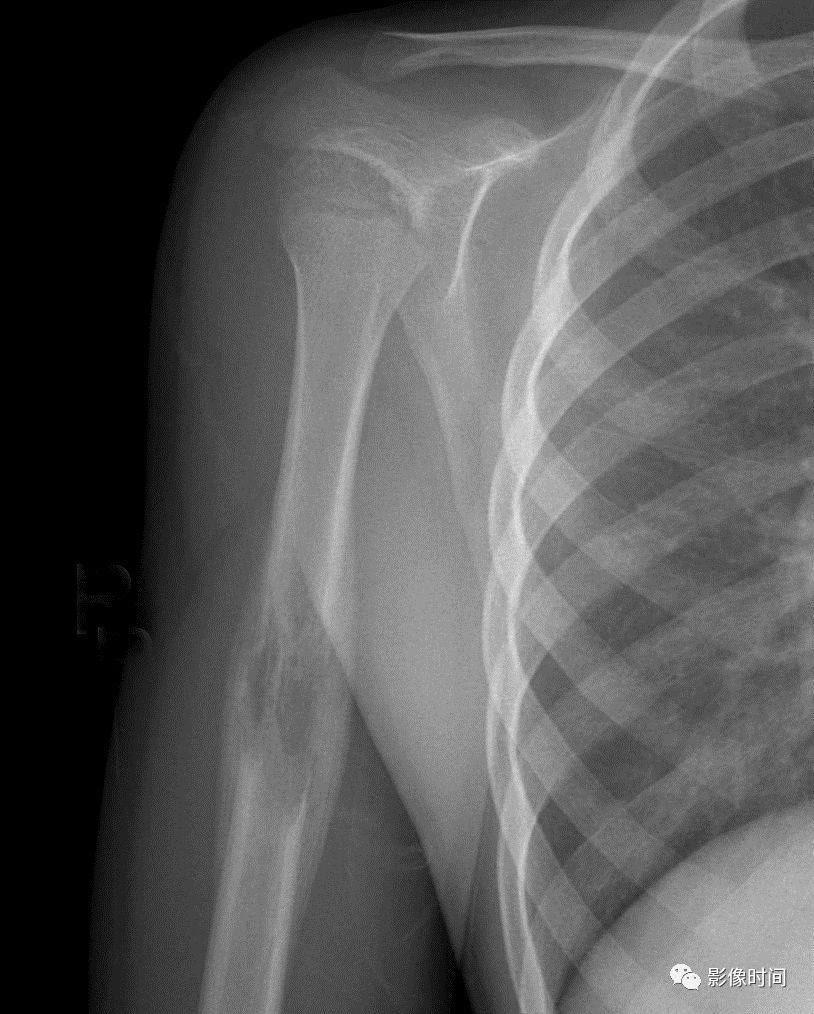

肿瘤对骨骺板和关节软骨的破坏是对骨破坏的继续。缺乏血管的骨骺板对恶性肿瘤有抵抗作用,骨骺板可暂时阻止肿瘤的蔓延,但当肿瘤进一步发展时, 骨骺板亦可被破坏,X 线平片或 CT 可表现为先期钙化带密度减低、中断或消失。MRI 可显示肿瘤从干骺端跨越骨骺板侵犯骨骺(图 15、图 16)。

肿瘤突破关节软骨向关节腔发展时, 可表现为关节面破坏、塌陷(图 17), 关节腔内出现软组织肿块。少数良性骨肿瘤如软骨母细胞瘤, 亦可超越骺板向两侧发展或突入关节腔内, 此为肿瘤膨胀生长所致, 而非浸润性破坏。

图 15  骨骺板破坏:骨肉瘤

图 16  骨骺板破坏:骨肉瘤

图 17  关节软骨破坏:骨肉瘤